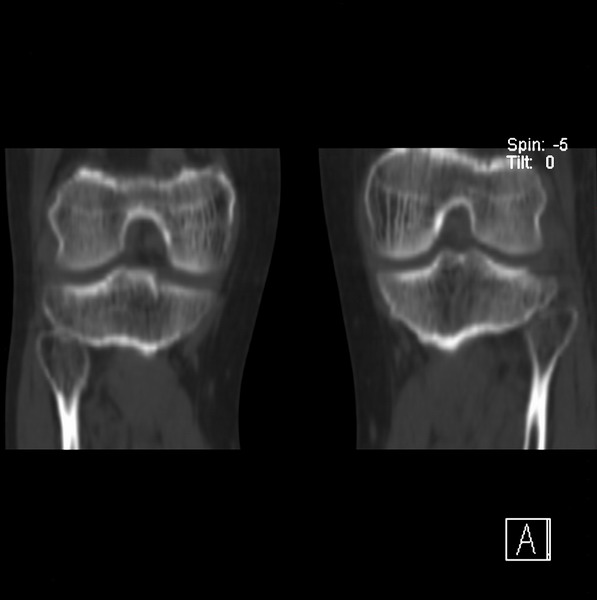

标题: CT21917:右腓骨小头是否骨软骨瘤? [打印本页]

标题: CT21917:右腓骨小头是否骨软骨瘤?

女、43.

不是骨软骨瘤,“牵拽征”,正常变异。有平片吗?

正常变异,“牵拽征”,比目鱼肌牵拽.

比目鱼肌附着点